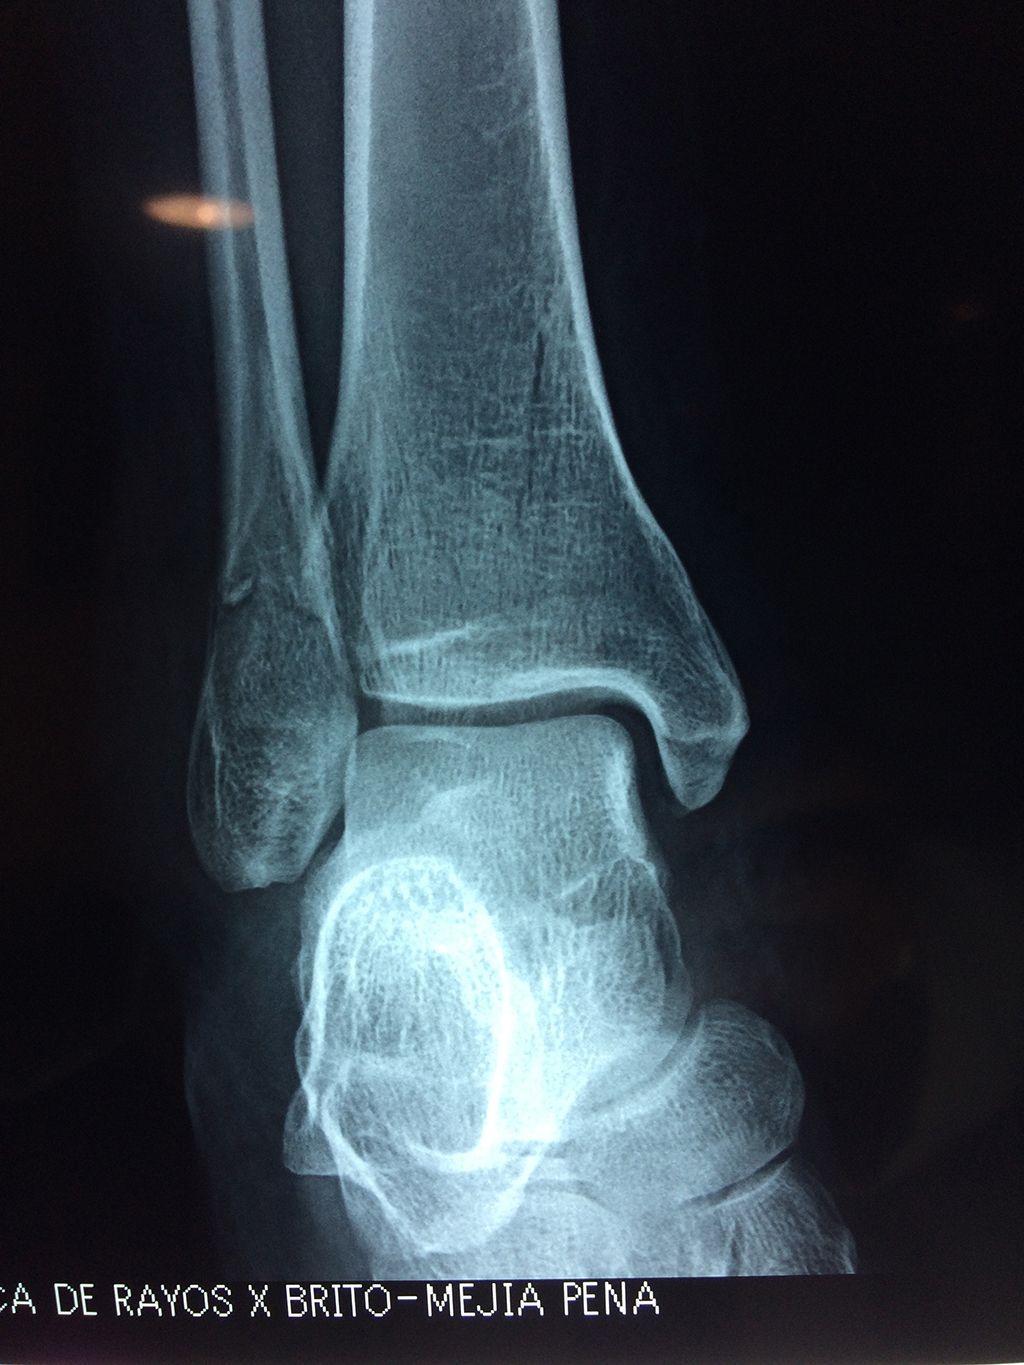

Una fractura de tobillo es la rotura de uno o más de los huesos del tobillo. Estas fracturas pueden ser:

- Parciales (el hueso está sólo parcialmente fisurado, no del todo).

- Completas (el hueso está perforado y está en 2 partes).

- Producirse en uno o ambos lados del tobillo.

Algunas fracturas de tobillo pueden requerir cirugía si:

- Los extremos de los huesos están desalineados entre sí (desplazados).

- La fractura se extiende hasta la articulación del tobillo (fractura intra-articular).